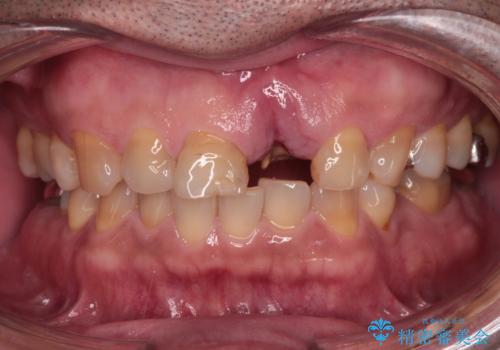

歯茎に溝が 大きく欠損した前歯のインプラント補綴治療

- 歯が朽ちてしまい、歯茎に大きな溝ができていることを気にして来院された患者様です。

インプラント治療を希望されておりましたが、軟組織の欠損が非常に大きいため、骨の回復を待ちながら歯肉の形態を整えていくこととしました。

歯肉形態を概ね回復するタイミングでインプラントを埋入し、補綴治療を行うこととしました。